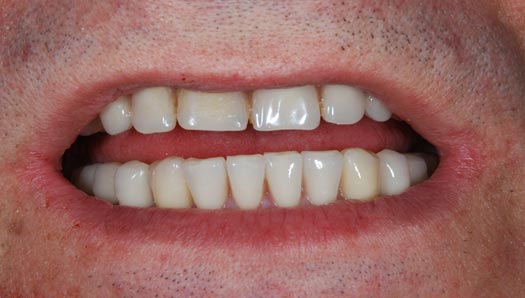

Con protesi fissa superiore e protesi fissa inferiore

I denti irrecuperabili dell'arcata superiore ed inferiore del paziente di anni 65

sono stati sostituiti da 10 impianti, cioè protesi radicolari endo-ossee che sostengono le protesi fisse superiore ed inferiore.